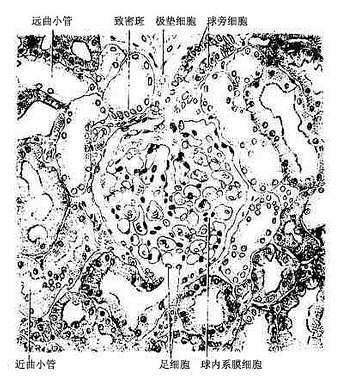

1.肾小体 肾小体(renal corpuscle)似球形,故又称肾小球,直径约200μm,由肾小囊和血管球组成(图15-3,15-4)。肾小体有两端或谓两极,微动脉出入的一端称血管极,另一端在血管极的对侧,肾小囊与近端小管相连接称尿极。

图15-4 肾皮质(高倍)

球旁复合体(juxtaglomerular complex)也称肾小球旁器(juxtaglomerular apparatus)由球旁细胞、致密斑和球外系膜细胞组成。它位于肾小体的血管极处,大致呈三角形,致密斑为三角形的底,入球微脉和出球微动脉分别形成三角形的两个侧边,球外系膜细胞则位三角区的中心(图15-3,15-13)。

图15-13 肾小体和球旁复合体模式图